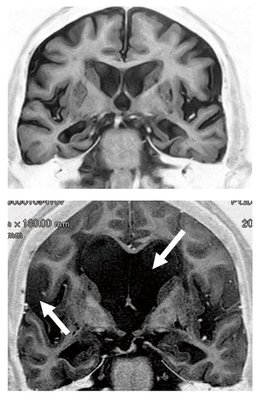

水頭症のひと 脳神経外科の病気:水頭症 | 病気の治療 | 徳洲会グループの詳細情報

脳神経外科の病気:水頭症 | 病気の治療 | 徳洲会グループ。特発性正常圧水頭症(とくはつせいせいじょうあつすいとうしょう。診断と検査|高齢者の水頭症 iNPH.jp。iNPHとは?|高齢者の水頭症 iNPH.jp。絵画の種類...油彩画・油絵形式...掛け軸・掛軸主題...人物・肖像壁掛けアート贄田越郎画主な画材...油彩絵の具